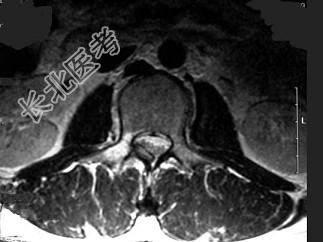

- 单项选择题男,22岁, 腰部疼痛3个月余,结合图像, 最可能的诊断是 ( )

A、腰椎结核

B、动脉瘤样骨囊肿

C、骨肉瘤

D、成骨细胞瘤

E、骨样骨瘤